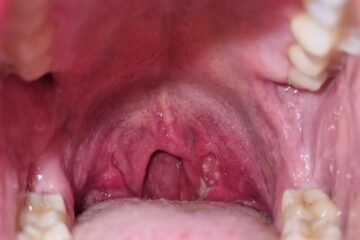

Maksts un dzimumlocekļa kandidoze ir bieži sastopama sēnīšu infekcija, kas attīstās, ja organismā pārmērīgi savairojas dabiski sastopamās Candida sēnes. Visbiežākās pazīmes ir nieze, dedzināšanas sajūta, izdalījumi un sāpes. Šie simptomi var skart gan sievietes, gan vīriešus atkarībā no tā, kurā zonā sēne izraisa iekaisumu.

Sēnīšu infekcija nereti sākas ar viegliem, grūti pamanāmiem simptomiem, kas ar laiku pastiprinās, ja netiek veikta ārstēšana. Tipiskākās izpausmes ir neparasti izdalījumi, izteikta nieze un nepatīkama dedzināšana dzimumorgānu apvidū. Daļai pacientu rodas arī sāpes urinēšanas laikā vai dzimumakta laikā.

Lai gan pamatpazīmes abiem dzimumiem mēdz būt līdzīgas, atsevišķas izpausmes atšķiras. Vīriešiem sēnīšu infekcija nereti izskatās kā balts vai spīdīgs laukums uz dzimumlocekļa galviņas. Ja vīrietis nav apgraizīts, tūskas vai kairinājuma dēļ var kļūt apgrūtināta priekšādiņas atvilkšana. Sievietēm biežāk sastopams izteikts kairinājums, tūska un nieze ap maksti, bet izdalījumi parasti ir īpaši biezi un nevienmērīgi.